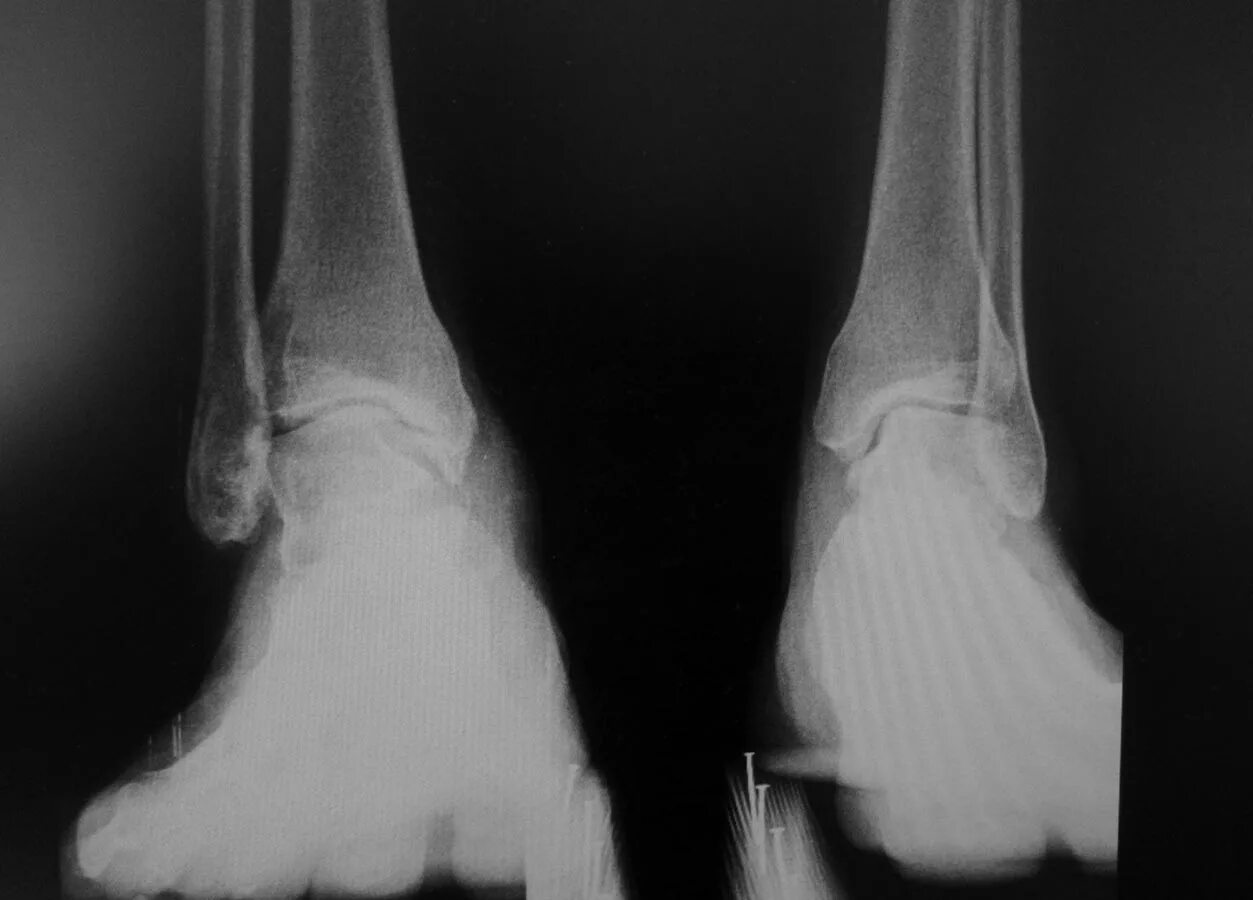

Артроз голеностопного сустава код